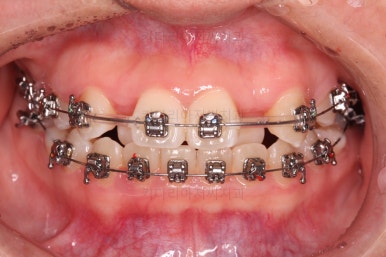

우선 장치를 저희 키다리아저씨치과에서 사용하는 장치로 바꿔 부착을 했어요.

세라믹에서 메탈로 안좋아진 것 아닌가요?

왼쪽이 처음 내원하셨을 당시의 입안 모습이고요. 오른쪽이 장치를 바꿔 부착한 이 후의 모습이에요.

세라믹에서 메탈로 다운그레이드 된 것처럼 보이죠?

사실은 훨씬 좋아진 장치랍니다.

유심히 보시면 왼쪽은 철사를 장치와 연결시키기 위해서 노란색 고무줄로 일일이 묶어줘야 하는 타입인데 비해, 오른쪽은 철사를 묶는 고무줄이 안보이죠?

바로 "자가결찰장치"라고 해서 브라켓에 일일이 뚜껑이 달려 있어서 철사를 장치 스스로가 직접 잡아주는 타입이에요.

그래서 메탈이라고 다 예전장치가 아니라는거죠.

메탈이라고 모두 예전 장치가 아니고 세라믹이라고 모두 최신 장치가 아닙니다.

자가결찰이 예전 장치에 비해 장점이 훨씬 많아서 아무리 세라믹이라고 한들 자가결찰 메탈이 훨씬 좋은 장치에요.

자가결찰 중에서도 재료가 메탈이 있고, 세라믹도 있어요.

(자가결찰 메탈, 자가결찰 세라믹 등)